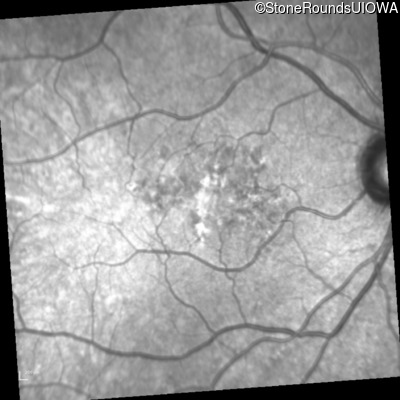

Infrared Fundus Photograph - Right - 20/25 +2

Exemplar